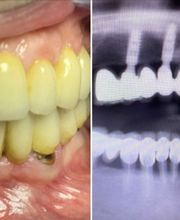

Lo studio dentistico del dr. Michele Piombino a Caserta offre la gamma più completa di servizi e specializzazioni in ambito odontoiatrico grazie alla pluriennale esperienza e all'impiego dei sistemi più evoluti e riconosciuti scientificamente a livello internazionale. Lo Studio Piombino offre ai propri pazienti trattamenti altamente specializzati e ad altissima affidabilità di implantologia osteointegrata, protesi estetiche e riabilitazioni totali fisse, anche nei grandi riassorbimenti ossei, proponendo trattamenti all inclusive immediati, quali ONE-DAY-TEETH, SYNCONE ALL-ON-FOUR, carico immediato impianti post-estrattivi. Presso lo studio Piombino è, inoltre, possibile eseguire trattamenti ortodontici fissi, mobili ed invisibili per la cura delle malocclusioni dento-scheletriche. Convenzionato con Previmedical, RSDA, Blue Assistance, Odontosalute, Odontonetwork.